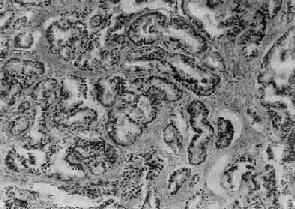

二、前列腺癌前列腺癌(carcinoma of prostate)多发生于60岁以上的老年人,在我国远较欧美国家少见。美国报告前列腺癌的死亡率占恶性肿瘤死亡率的第二位,在我国前列腺癌的发生率只占恶性肿瘤的0.3%左右。 【病因】 前列腺癌的病因尚不十分清楚,一般认为激素特别是雄激素可能起重要作用。长期以来各家对前列腺癌与前列腺增生之间的关系看法不一。目前大多数学者认为两者间无明显关系,因为前列腺癌很少发生于良性增生的前列腺内。在组织发生上增生与癌的发生部位也不相同,前列腺增生多发生于尿道周围部的前列腺组织(即前列腺内区);而前列腺癌几乎都开始发生于前列腺的包膜下部(即前列腺外区),该部组织对雄激素敏感,高水平的雄激素可使该部增生。据统计,阉人不发生前列腺癌,这些都支持雄激素和前列腺癌有关。但前列腺癌患者多为老年人,睾丸产生的雄激素已经降低,所以仍有不支持此说的根据。有人假设前列腺癌发展很慢,可以长期处在潜伏状态,可能在雄激素尚处于较高水平时即已发生小的癌灶,发展到老年才出现症状,这一假设尚有待进一步验证。 【病变】 肉眼观,前列腺癌初期为单个或多数的硬结节,其前列腺可以增大,也可正常大小。早期病灶几乎都发生于包膜下,其中大多数发生于后叶,其次是两侧及前叶的包膜下,而发生于中叶者极为少见。晚期肿瘤可扩展到全部前列腺,使前列腺明显增大而质地变硬。切面灰白色夹杂以多少不等的纤维性条纹或间隔,也可呈均质性夹以不规则的黄色区域。 镜下,97%的前列腺癌均为腺癌,少数为移行细胞癌和鳞状细胞癌。依其分化程度可分为高分化、中分化和低分化3型。高分化前列腺癌最多见,癌细胞排列成大小不等的腺样结构,颇似前列腺增生腺体,但癌细胞体积较小,核较深染,上皮细胞往往呈多层排列并较不规则(图14-4),有时可呈乳头状腺癌或腺泡腺癌结构,并常可见癌组织向间质浸润生长;中分化腺癌全部或部分呈腺样结构,但腺体排列较紊乱,核异型性较明显,且有时形成筛状结构;低分化腺癌的癌细胞一般较小,排列成实体团块或条索,腺腔样结构很少(图14-5)。多数病例乃由上述多种组织结构混合组成。

图14-5 前列腺癌(低分化型) 癌细胞异型明显,并呈筛状结构 【转移及扩展】 前列腺癌的蔓延和转移与癌细胞分化程度有一定关系。高分化腺癌蔓延和转移较晚,可长期局限于前列腺内,预后较好。分化较差的腺癌可直接侵犯周围器官,如膀胱底、精囊腺、尿道等,但很少直接侵入直肠,因癌组织不易穿透直肠膀胱筋膜。前列腺癌的淋巴结转移比较常见,最常侵犯的淋巴结有髂内、髂外、腹主动脉旁、腹股沟等淋巴结,也可侵入胸导管、锁骨下淋巴结等处。血行转移可转移至骨、肺、肝等处,特别是腰椎、骨盆及肋骨的转移较常见。骨转移的途径有认为是经肺循环后再散布到全身的骨及肝组织,也有认为可经脊椎静脉丛直接转移至腰椎。 前列腺癌可分泌酸性磷酸酶,临床上常以此作为前列腺癌的一个检测指标。